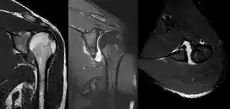

A diagnosis of shoulder dislocation is often suspected based on the person's history and physical examination. Radiographs are made to confirm the diagnosis. Most dislocations are apparent on radiographs showing incongruence of the glenohumeral joint. Posterior dislocations may be hard to detect on standard AP radiographs, but are more readily detected on other views. After reduction, radiographs are usually repeated to confirm successful reduction and to detect bone damage. After repeated shoulder dislocations, an MRI scan may be used to assess soft tissue damage. In regards to recurrent dislocations, the apprehension test (anterior instability) and sulcus sign (inferior instability) are useful methods for determining predisposition to future dislocation.

A Hill–Sachs lesion is an impaction of the head of the humerus left by the glenoid rim during dislocation.[6] Hill-Sachs deformities occur in 35–40% of anterior dislocations. They can be seen on a front-facing X-ray when the arm is in internal rotation.[9] Bankart lesions are disruptions of the glenoid labrum with or without an avulsion of bone fragment.